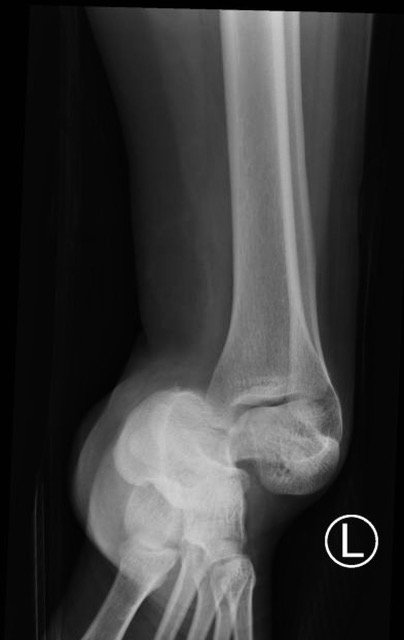

The X-rays were significant for a subtalar dislocation. The calcaneus (red) is laterally displaced with respect to the talar head (orange), and the white lines indicate the normal articular surface. Additionally, there was a talonavicular dislocation, as seen in the fourth image: the talus (green) and navicular bone (purple) overlapping suggests a dislocation. In a normally aligned foot, the boundaries of the two bones create a point of articulation.

Proper diagnosis of talonavicular dislocations require obtaining anteroposterior (AP), lateral, and mortise views of the ankle and foot.3 The utility of computed tomography (CT) in diagnosis has also been discussed. One study reported that 44% of patients who received CT for subtalar dislocation had a treatment plan differing from that based on plain film findings.4 Specifically, CT identified fractures that were not visible on plain films as well as intraarticular debris requiring evacuation in an effort to promote proper healing and function.